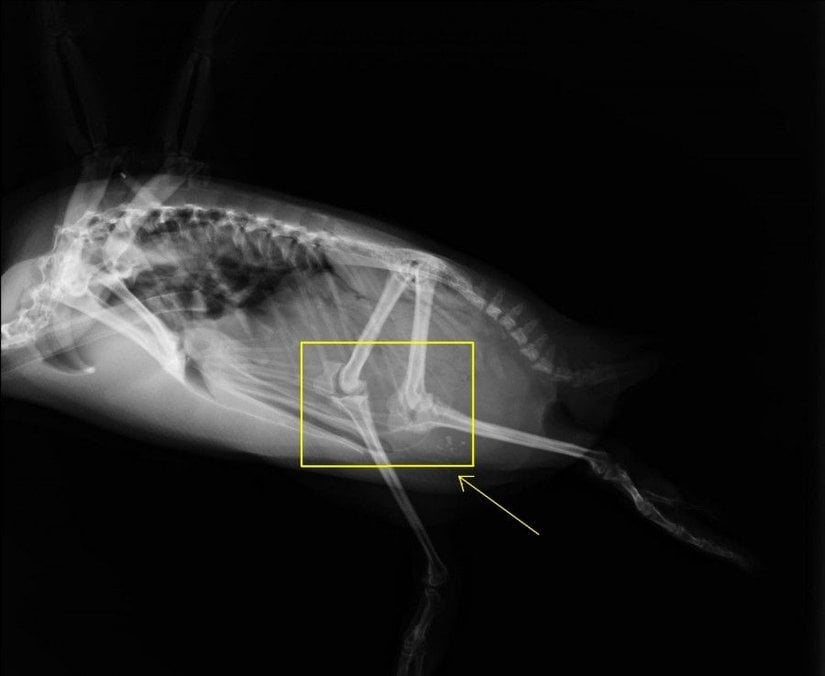

Elbette hayır. Fotoğrafta gördüğünüz bir penguenin X-Işını Taraması altındaki bacak kemiklerinin görüntüsü.

Penguenlerin dizleri, vücutlarının içerisinde yer alır; dışarıdan gözükmez. Ancak dikkatli bir inceleme, evrimsel öngörünün tam da ileri sürdüğünün penguenler için de geçerli olduğunu ortaya çıkaracaktır: Penguenler de, diğer tüm omurgalılarla aynı vücut planını paylaşmaktadır.